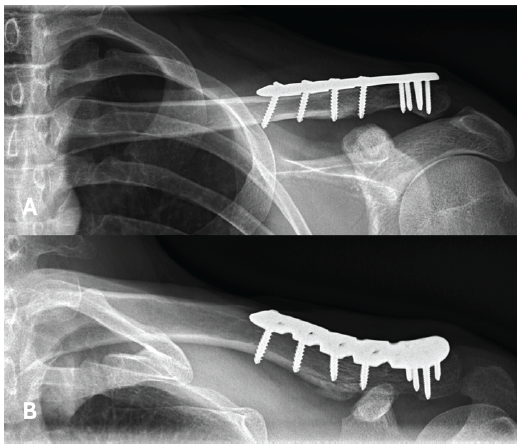

Given the improved bone stock of the lateral fragment, locking plate osteosynthesis was chosen as treatment. Coracoclavicular reconstruction was deemed unnecessary, as the lateral fragment remained stable. Both the surgery and post-operative course were uneventful through the 3-month follow-up, and the fracture at the site of the bone groove had nearly completely healed (Fig. 5).

Figure 5: X-rays at the final follow-up, 3 months after plate osteosynthesis, showing good healing of the fracture.